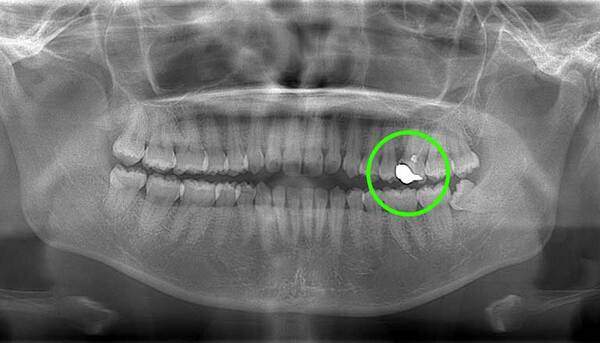

麻布十番歯科で親知らずのレントゲン画像のイメージ

左上の親知らずですが、真っ直ぐはえています。

口腔内では大きな虫歯になっていましたので、抜歯の適応となります。